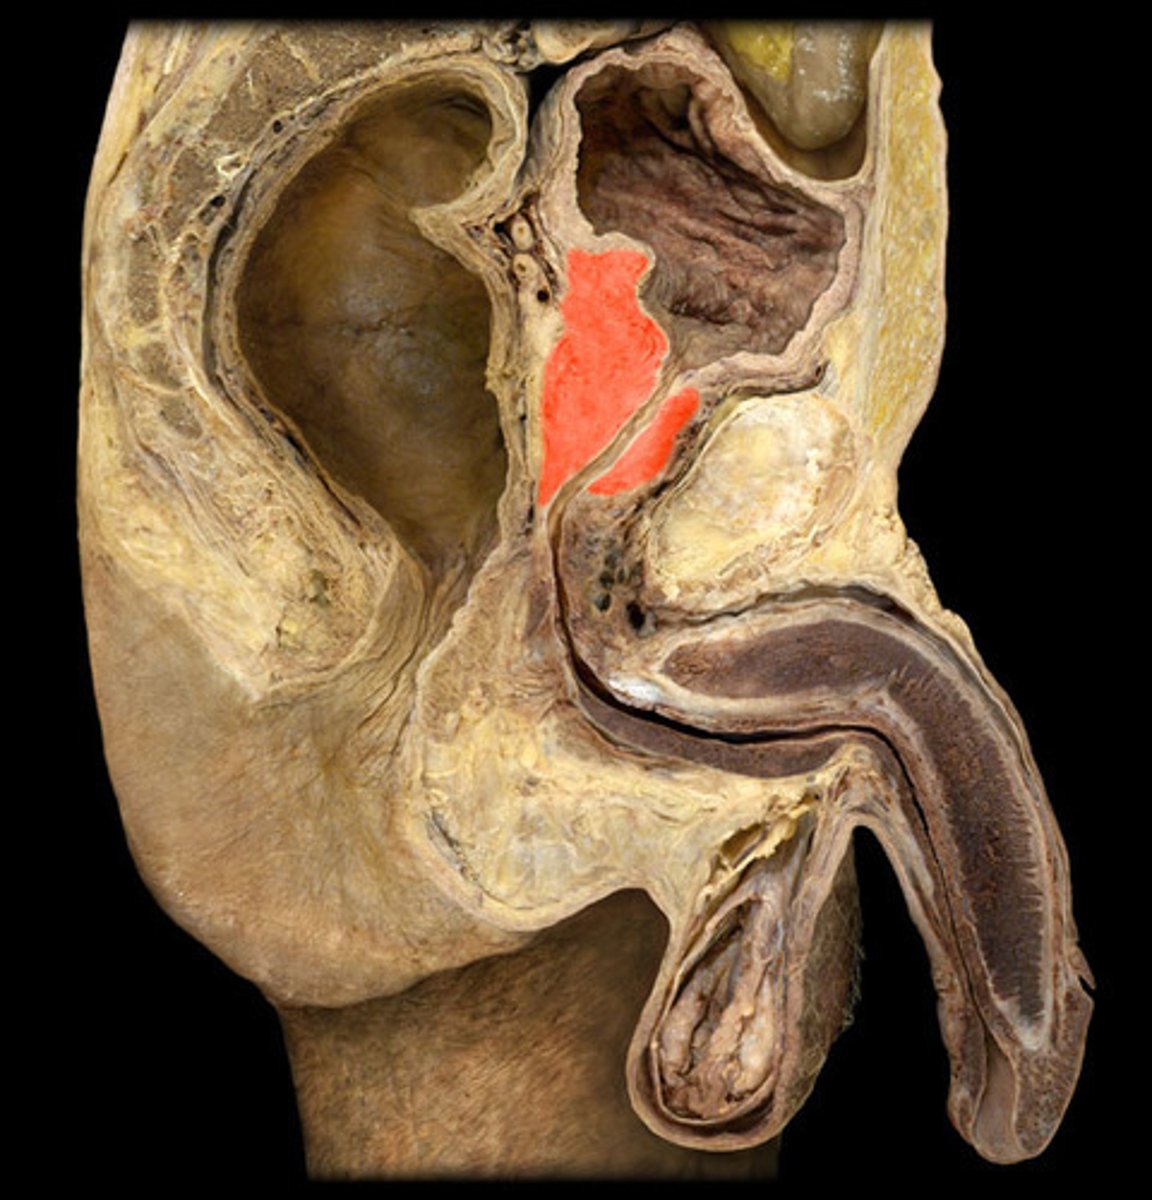

Testis

Epididymis

Spermatic Cord

Vas Deferens

Seminal Vesicle

Prostate

Penis

Corpus Cavernosum

Glans Penis